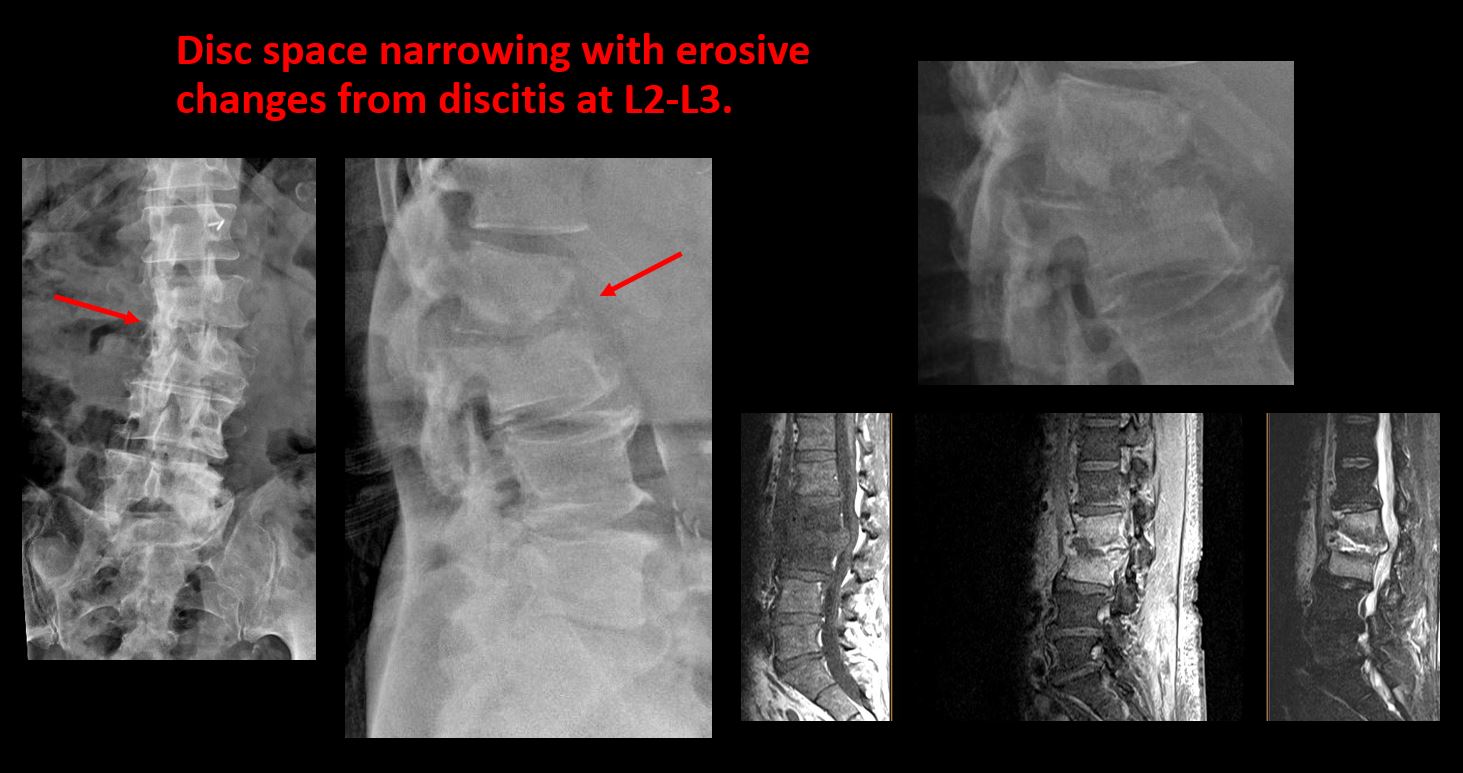

Section 1 Submit Findings CB1239 Findings Technique The thoracolumbar junction and/or the lumbosacral junction is/are not entirely included on the exam. Yes No The exam is over or under penetrated. Yes No The exam is limited by overlying structures, bones or soft tissues, patient positioning, support devices, or motion. Yes No Prevertebral and paravertebral soft tissues The prevertebral or paravertebral soft tissues are abnormal. Yes No Spinal alignment The vertebral bodies are abnormally aligned. Yes No The anterior and posterior vertebral body lines are abnormal or interrupted. Yes No The visualized spinous processes are malaligned or distracted on the AP and/or lateral view(s). Yes No There is reversal or straightening of the normal lordosis or scoliosis of the lumbar spine. Yes No Vertebral bodies, posterior elements and included sacral segments There are more or less than the expected 5 non rib-bearing vertebral bodies. Yes No There is a transitional motion segment at the lumbosacral junction (sacralization of L5 or lumbarization of S1). Yes No There is a fracture or distraction of a vertebral body, transverse or spinous process, or other posterior element. Yes No There is anterior wedging and/or compression of a vertebral body or end plate. Yes No There is an end plate avulsion or other fracture. Yes No There is displacement of a fracture fragment into the soft tissues or spinal canal. Yes No There is lucency or defect of the pars interarticularis from spondylolysis. Yes No There is an abnormality of a pedicle or lamina on the frontal or lateral view. Yes No There is a fracture, erosion, sclerosis, lytic, or blastic lesion of a pedicle or lamina. Yes No There is evidence of a lytic or sclerotic lesion, or disruption of the trabecular pattern of a vertebral body, end plate, or sacrum. Yes No There is a fracture or interruption of the arcuate lines of the sacrum. Yes No There is erosion, sclerosis, narrowing, or other abnormality of a sacral foramen or the SI joints. Yes No There is focal or diffuse abnormal mineralization of the lumbosacral spine. Yes No Disc spaces and facet joints There is distraction or focal widening of a disc space. Yes No There is disc space narrowing with or without erosive or sclerotic changes of the end plates or subchondral bone other than from degenerative change. Yes No There is anterior or posterior spondylolisthesis, subluxation, or rotational abnormality at a disc space. Yes No There is widening, rotational abnormality, or displacement of facets at any motion segment. Yes No There is facet joint narrowing or sclerosis other than from degenerative change. Yes No There is narrowing or encroachment of a neural foramen other than from degenerative change. Yes No There are degenerative changes present that might explain the patient’s symptoms. Yes No Additional soft tissues and bones (lower thorax, abdomen, and pelvis) There is abnormal bowel or bowel gas pattern. Yes No There are gallstones, vascular, renal, pelvic, or other soft tissue calcifications present. Yes No There is free intraperitoneal or retroperitoneal air or other abnormal air in the included chest, abdomen, or pelvis. Yes No The included thoracic spine, ribs, and remainder of the bony pelvis are abnormal. Yes No There is abnormality of the lower chest and/or diaphragm. Yes No There is a foreign body or there are post surgical changes of the bones or soft tissues of the included lower thorax, abdomen, and pelvis. Yes No There is an abnormality or complication of post surgical hardware/device. Yes No N/A There are support lines or tubes in an abnormal position. Yes No Other findings There are other existing conditions that might be contributing to symptoms which can or should be further evaluated non-emergently. Yes No